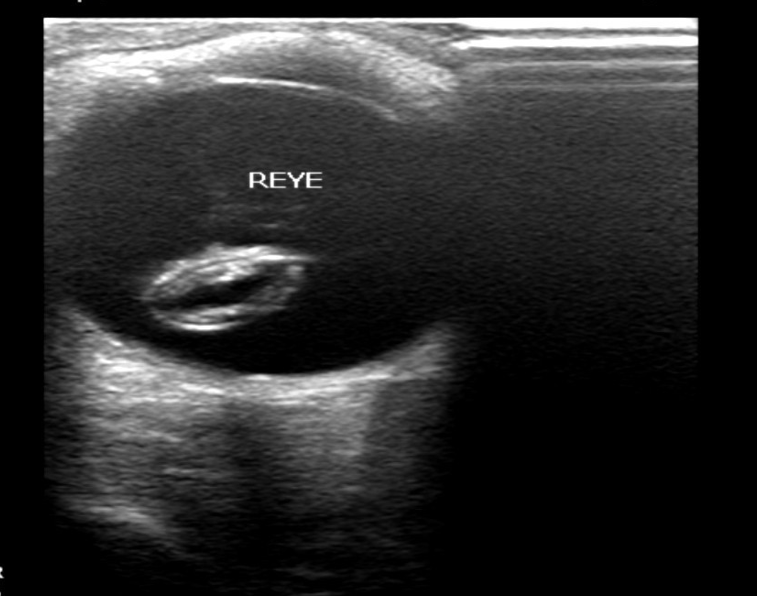

图 6 晶状体全脱位二维超声表现

图片来源:作者提供